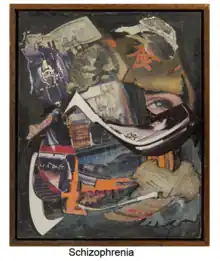

Schizophrenia

Schizophrenia is known to affect attention, perception, memory, learning, processing, reasoning, and problem solving.[152]

Schizophrenia has been linked to impaired face and emotion perception.[152][153][154][91] People with schizophrenia demonstrate worse accuracy and slower response time in face perception tasks in which they are asked to match faces, remember faces, and recognize which emotions are present in a face.[91] People with schizophrenia have more difficulty matching upright faces than they do with inverted faces.[152] A reduction in configural processing, using the distance between features of an item for recognition or identification (e.g. features on a face such as eyes or nose), has also been linked to schizophrenia.[91]

Schizophrenia patients are able to easily identify a "happy" affect but struggle to identify faces as "sad" or "fearful".[154] Impairments in face and emotion perception are linked to impairments in social skills, due to the individual's inability to distinguish facial emotions.[154][91] People with schizophrenia tend to demonstrate a reduced N170 response, atypical face scanning patterns, and a configural processing dysfunction.[155] The severity of schizophrenia symptoms has been found to correlate with the severity of impairment in face perception.[91]

Individuals with diagnosed schizophrenia and antisocial personality disorder have been found to have even more impairment in face and emotion perception than individuals with just schizophrenia. These individuals struggle to identify anger, surprise, and disgust. There is a link between aggression and emotion perception difficulties for people with this dual diagnosis.[154]

Data from magnetic resonance imaging and functional magnetic resonance imaging has shown that a smaller volume of the fusiform gyrus is linked to greater impairments in face perception.[153]

There is a positive correlation between self-face recognition and other-face recognition difficulties in individuals with schizophrenia. The degree of schizotypy has also been shown to correlate with self-face difficulties, unusual perception difficulties, and other face recognition difficulties.[156] Schizophrenia patients report more feelings of strangeness when looking in a mirror than do normal controls. Hallucinations, somatic concerns, and depression have all been found to be associated with self-face perception difficulties.[157]